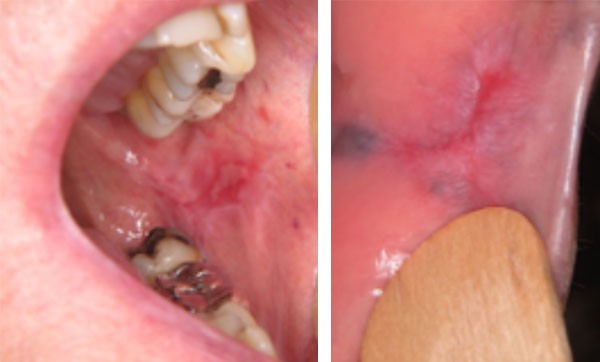

Examen clinique. On observait une ulcération jugale gauche bordée par un érythème et un réseau kératosique blanchâtre. La lésion était située en regard de restaurations dentaires à l’amalgame et d’une couronne métallique. L’examen de la joue droite montrait un réseau kératosique et la langue présentait des plaques kératosiques. La palpation de la muqueuse en regard des lésions ne retrouvait aucune induration.

Examen paraclinique. Une biopsie a été réalisée au niveau de l’érythème et de la kératose de la joue droite. Elle mettait en évidence une réaction lichénoïde caractérisée par un infiltrat lympho-plasmocytaire sous la membrane basale de l’épithélium.